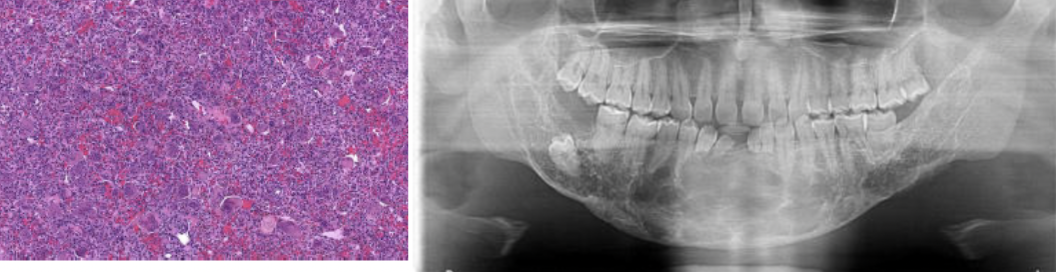

Give one diagnosis for this case:

A

Histology shows multinucleated giant cells

A: central giant cell granuloma